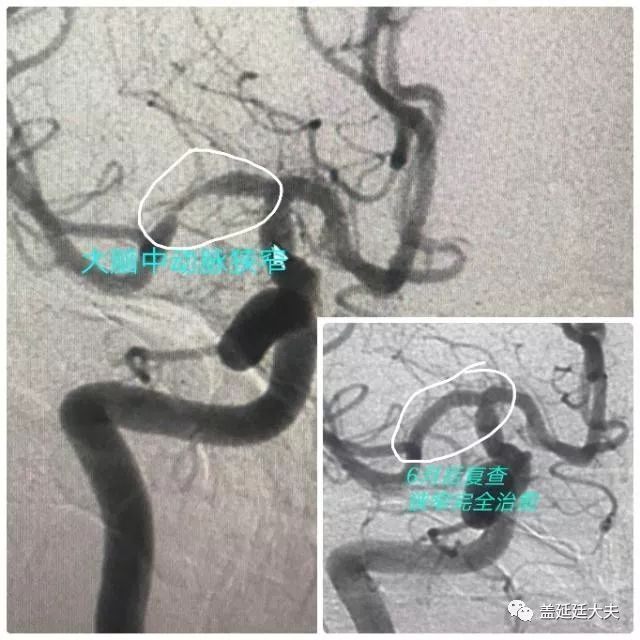

一是半年前治疗的颅内大脑中动脉狭窄患者复查造影发现狭窄完全治愈,血管完全修复!